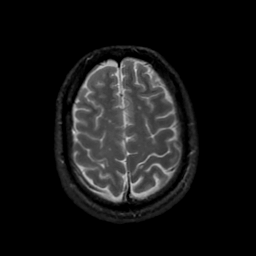

MR Study #22, December 1, 1991 -- Slice #40

[Home][Help][Clinical][Tour 1][Tour 2] Slice 40